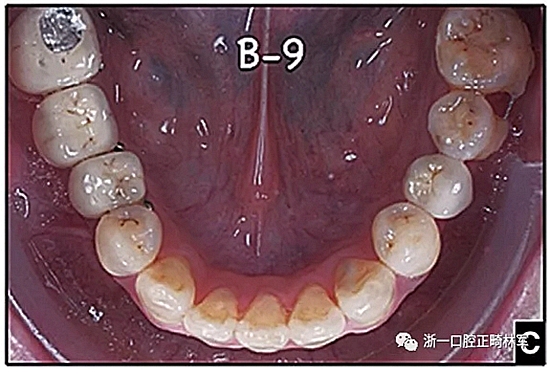

圖15.A,去除固定裝置一個月后,下頜左側(cè)第二前磨牙復(fù)發(fā),移動到種植體愈合的部位; B,B-0表示開始再治療,通過鏈圈和推簧的矯正復(fù)發(fā); C,B-9是治療結(jié)束后3個月回訪時下頜弓的咬合面觀,這是再治療階段的9個月。下頜左側(cè)第二前磨牙和第三磨牙的頰面粘合一個固定保持器,以防止復(fù)發(fā)。